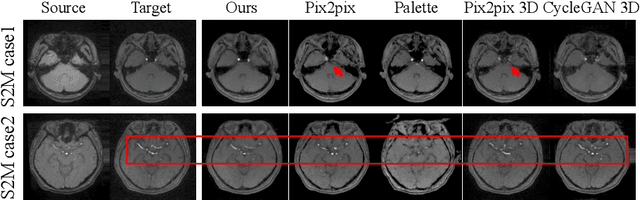

Abstract:Cross-modality medical image synthesis is a critical topic and has the potential to facilitate numerous applications in the medical imaging field. Despite recent successes in deep-learning-based generative models, most current medical image synthesis methods rely on generative adversarial networks and suffer from notorious mode collapse and unstable training. Moreover, the 2D backbone-driven approaches would easily result in volumetric inconsistency, while 3D backbones are challenging and impractical due to the tremendous memory cost and training difficulty. In this paper, we introduce a new paradigm for volumetric medical data synthesis by leveraging 2D backbones and present a diffusion-based framework, Make-A-Volume, for cross-modality 3D medical image synthesis. To learn the cross-modality slice-wise mapping, we employ a latent diffusion model and learn a low-dimensional latent space, resulting in high computational efficiency. To enable the 3D image synthesis and mitigate volumetric inconsistency, we further insert a series of volumetric layers in the 2D slice-mapping model and fine-tune them with paired 3D data. This paradigm extends the 2D image diffusion model to a volumetric version with a slightly increasing number of parameters and computation, offering a principled solution for generic cross-modality 3D medical image synthesis. We showcase the effectiveness of our Make-A-Volume framework on an in-house SWI-MRA brain MRI dataset and a public T1-T2 brain MRI dataset. Experimental results demonstrate that our framework achieves superior synthesis results with volumetric consistency.